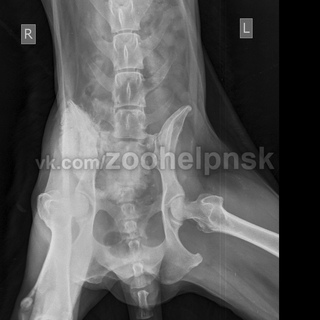

Рентгенография является необходимым методом диагностики остеосарком у собак. Для идентификации малейших изменений на ранних стадиях развития костных опухолей нужна очень хорошая техника, поскольку увеличение необходимо при исследовании костных трабекул. Для съемки иногда может потребоваться седация, так как костные опухоли очень болезненны, что может вызывать затруднения при правильном позиционировании животного. При проведении рентгенографического обследования можно выявить следующие характерные признаки остеосарком у собак:

- Остеопластические и остеолитические проявления рака кости.

- Слабо выраженные края областей разрушения кости.

- Утончение и лизис кортикального слоя.

- Появление «треугольника Кодмана» и радиальные шипы в виде «солнечных лучей», так называемые «спикулы».

- Пятнистый склероз (повышение плотности кости).

- Длинные переходы зоны к нормальной кости, никаких перегородок.

- Отек мягких тканей и пр.

Лизис бедра